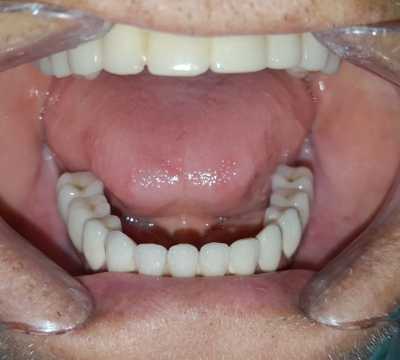

Pacient in varsta de 67 de ani, cunoscut cu boala parodontala severa cu mobilitate avansata a tuturor dintilor, care se prezinta in cadrul clinicii noastre atat din motive functionale, cat si estetice.

Acesta a optat pentru extractia dintilor afectati si protezarea fixa cu ajutorul implanturilor dentare, pacientul dorind respectarea formei si a culorii danturii proprii. Avand in vedere pierderea osoasa importanta, cauzata de patologia pacientului, acesta a necesitat in vederea reabilitarii, atat de sinus lift extern, cat si de aditie osoasa cu os artificial si membrana de colagen.

S-au inserat 10 implanturi dentare la nivel maxilar si 7 la nivel mandibular, pe baza carora s-au realizat protezari fixe metalo-cermice mandibular si ceramica pe zirconiu la nivel maxilar.

N.B. Cel de-al 7-lea implant mandibular a fost inserat la o luna distanta de la interventia initiala- defectul osos local fiind prea avansat pentru inserarea implantului in acelasi timp operator.